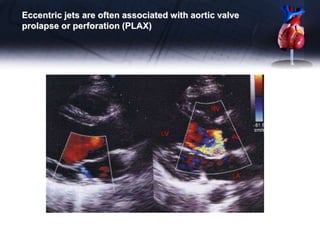

Colour flow imaging •Using colour flow Doppler, the regurgitant jet into the LV during diastole can be visualized from multiple views. • The colour jet area and length are weakly correlated to the degree of AR, are affected by the aortic to LV diastolic pressure gradient and LV compliance, and are often overestimated in the apical views. • Central jets are suggestive of rheumatic disease • Eccentric jets are often associated with aortic valve prolapse or perforation.

• 56.

• 57.

Eccentric jets areoften associated with aortic valve prolapse or perforation (PLAX)